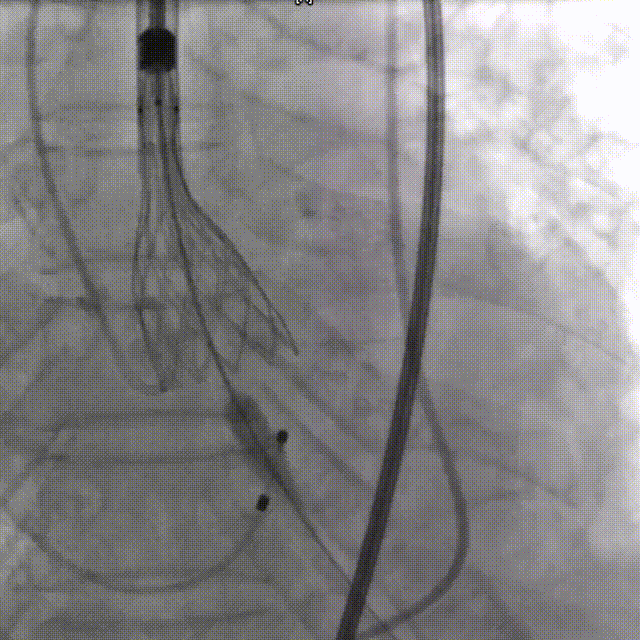

输送器过弓

瓣下3mm定位

左冠窦侧偏深,需回收再定位

回收调整至零位定位,释放到工作位位置合适

完全释放后无反流,冠脉灌注良好